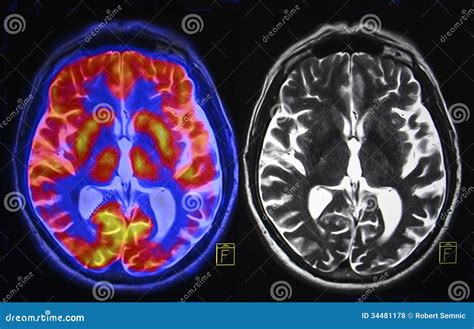

Brain scans are diagnostic tools that allow medical professionals to visualize the brain's structure and activity. They are essential for diagnosing and monitoring various neurological conditions, planning surgical procedures, and conducting research. The primary types of brain scans include Magnetic Resonance Imaging (MRI), Computed Tomography (CT), Positron Emission Tomography (PET), and Functional MRI (fMRI). Each of these techniques offers unique advantages and is used in different clinical and research settings.

MRI is one of the most commonly used types of brain scans. It uses powerful magnets and radio waves to create detailed images of the brain's structure. MRI scans are particularly useful for detecting tumors, aneurysms, and other abnormalities. They provide high-resolution images that can reveal even the smallest details of brain tissue.

PET scans use a radioactive tracer to visualize metabolic processes in the brain. They are particularly useful for detecting cancer, assessing brain function, and studying neurological disorders such as Alzheimer's disease and Parkinson's disease. PET scans provide information about the brain's biochemical activity, making them invaluable for research and diagnosis.

PET scans are often combined with CT or MRI scans to provide both structural and functional information. This combination allows for a more comprehensive understanding of the brain's condition.

fMRI is a specialized type of MRI that measures brain activity by detecting changes in blood flow. It is particularly useful for studying cognitive functions, such as language, memory, and motor control. fMRI scans provide real-time information about brain activity, making them invaluable for research and clinical applications.